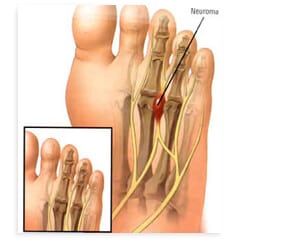

Mortonse neuralgie

Wat is Mortonse neuralgie Een Mortonse neuralgie is een zenuwbeknelling tussen twee middenvoetsbeentjes. De beknelde zenuw raakt hierdoor geïrriteerd . Meestal betreft het de zenuw tussen het 3e en 4e middenvoetsbeentje, soms ook tussen het 2e en 3e...